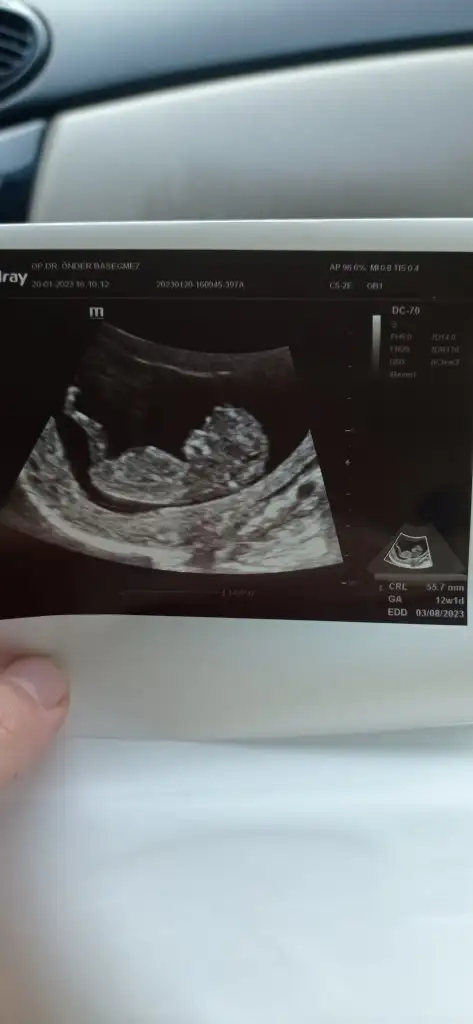

Nub,skull ve cinsiyet

bana da bakar mısınız ☺️

Sizinki nubunu kapatmis ben goremedim ama icime erkek dogdu nedense ilerleyen zamnda giderseniz tekrar foto atarmisiniz

• IMG_20230120_162528.webp

IMG_20230120_162528.webp

11,8 KB · Görüntüleme: 96